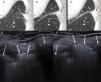

A-C) La TC en controles seriados mostró una opacidad pulmonar periférica laterobasal izquierda con discreta extensión al espacio intercostal que había aumentado de tamaño y densidad progresivamente (flechas negras). D) La ecografía torácica (sin maniobra de Valsalva) demostró la presencia de una lesión hiperecogénica (flechas blancas) en el espacio intercostal entre los arcos laterales de la séptima y octava costillas izquierdas (flechas blancas dobles), que se movilizaba con la respiración. E) Al realizar maniobra de Valsalva, dicha lesión protruía significativamente hacia la pared torácica. El enfermo fue diagnosticado de hernia pulmonar intercostal probablemente con relación a la vía de entrada de la toracoscopia para la realización de una lobectomía superior izquierda.

Se presenta el caso de una mujer de 65 años de edad con antecedente de adenocarcinoma pulmonar estadio IB intervenido por videotoracoscopia realizando lobectomía superior izquierda. La paciente no presentaba dolor y la exploración física local de la herida quirúrgica fue normal. En último control mediante TC torácica, se visualizaba opacidad pulmonar periférica laterobasal izquierda de aproximadamente 24mm de longitud máxima, con discreta extensión al espacio intercostal, que había aumentado de tamaño y densidad respecto a la primera TC posquirúrgica (fig. 1). Este hallazgo radiológico fue orientado como una atelectasia pulmonar focal, sin poder descartar recidiva local de su enfermedad neoplásica. El caso fue presentado en el comité multidisciplinar de tumores torácicos de nuestro centro y se decidió realizar biopsia guiada mediante ecografía. La ecografía mostró la presencia de una hernia pulmonar intercostal entre la séptima y la octava costillas izquierdas, claramente demostrada en maniobra de Valsalva (fig. 1), correspondiente a la opacidad pulmonar periférica visualizada en las TC. La paciente permaneció asintomática en todo momento y se decidió actitud expectante.